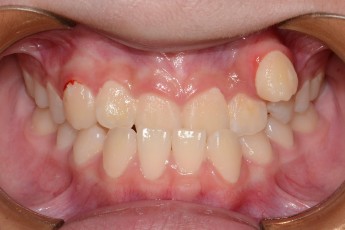

BEFORE & AFTER

- 성장교정